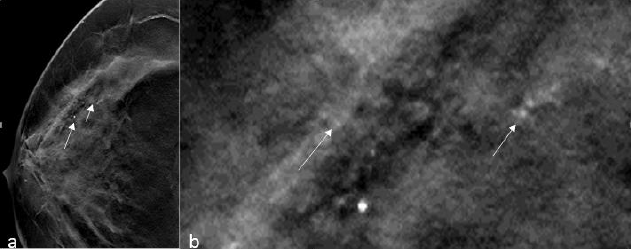

They are small and hazy in appearance without a specific shape. When they occur in a grouped, linear, or segmental distribution, they are deemed suspicious and commonly warrant biopsy. But when they appear in both breasts and are diffuse, they can be assigned a benign BIRADS category. According to ACR BIRADS, amorphous calcifications have a positive predictive value of 20 % and are therefore assigned the BIRADS 4b category [5]. Many studies have been done on assessing the efficiency of mammography imaging techniques in the characterization of amorphous calcifications and the utility of biopsy of these calcifications.

In a study by Ferreira et al. [15] 78 patients with suspicious grouped amorphous calcifications on mammography and categorized as BIRADS 4 were retrospectively analysed with their histopathology results with samples having been obtained via VABB. Their conclusion was that amorphous calcifications of a suspicious nature showed a correlation more with precursor lesions, than with malignancy with a ratio of 3:1.

In another study by Oligane et al. [16] published in 2018, they retrospectively analysed 497 lesions from 494 patients that underwent stereotactic biopsies based on the presence of amorphous calcifications. In their study, they found that 10.5% lesions were malignant with an association of the invasive cancers and hormone receptor positivity (Figure 12).

Figure 12:RMLO view and RMLO magnified view taken of a 64-year-old woman shows grouped amorphous calcifications. Image courtesy: HCG Hospitals, Bangalore.